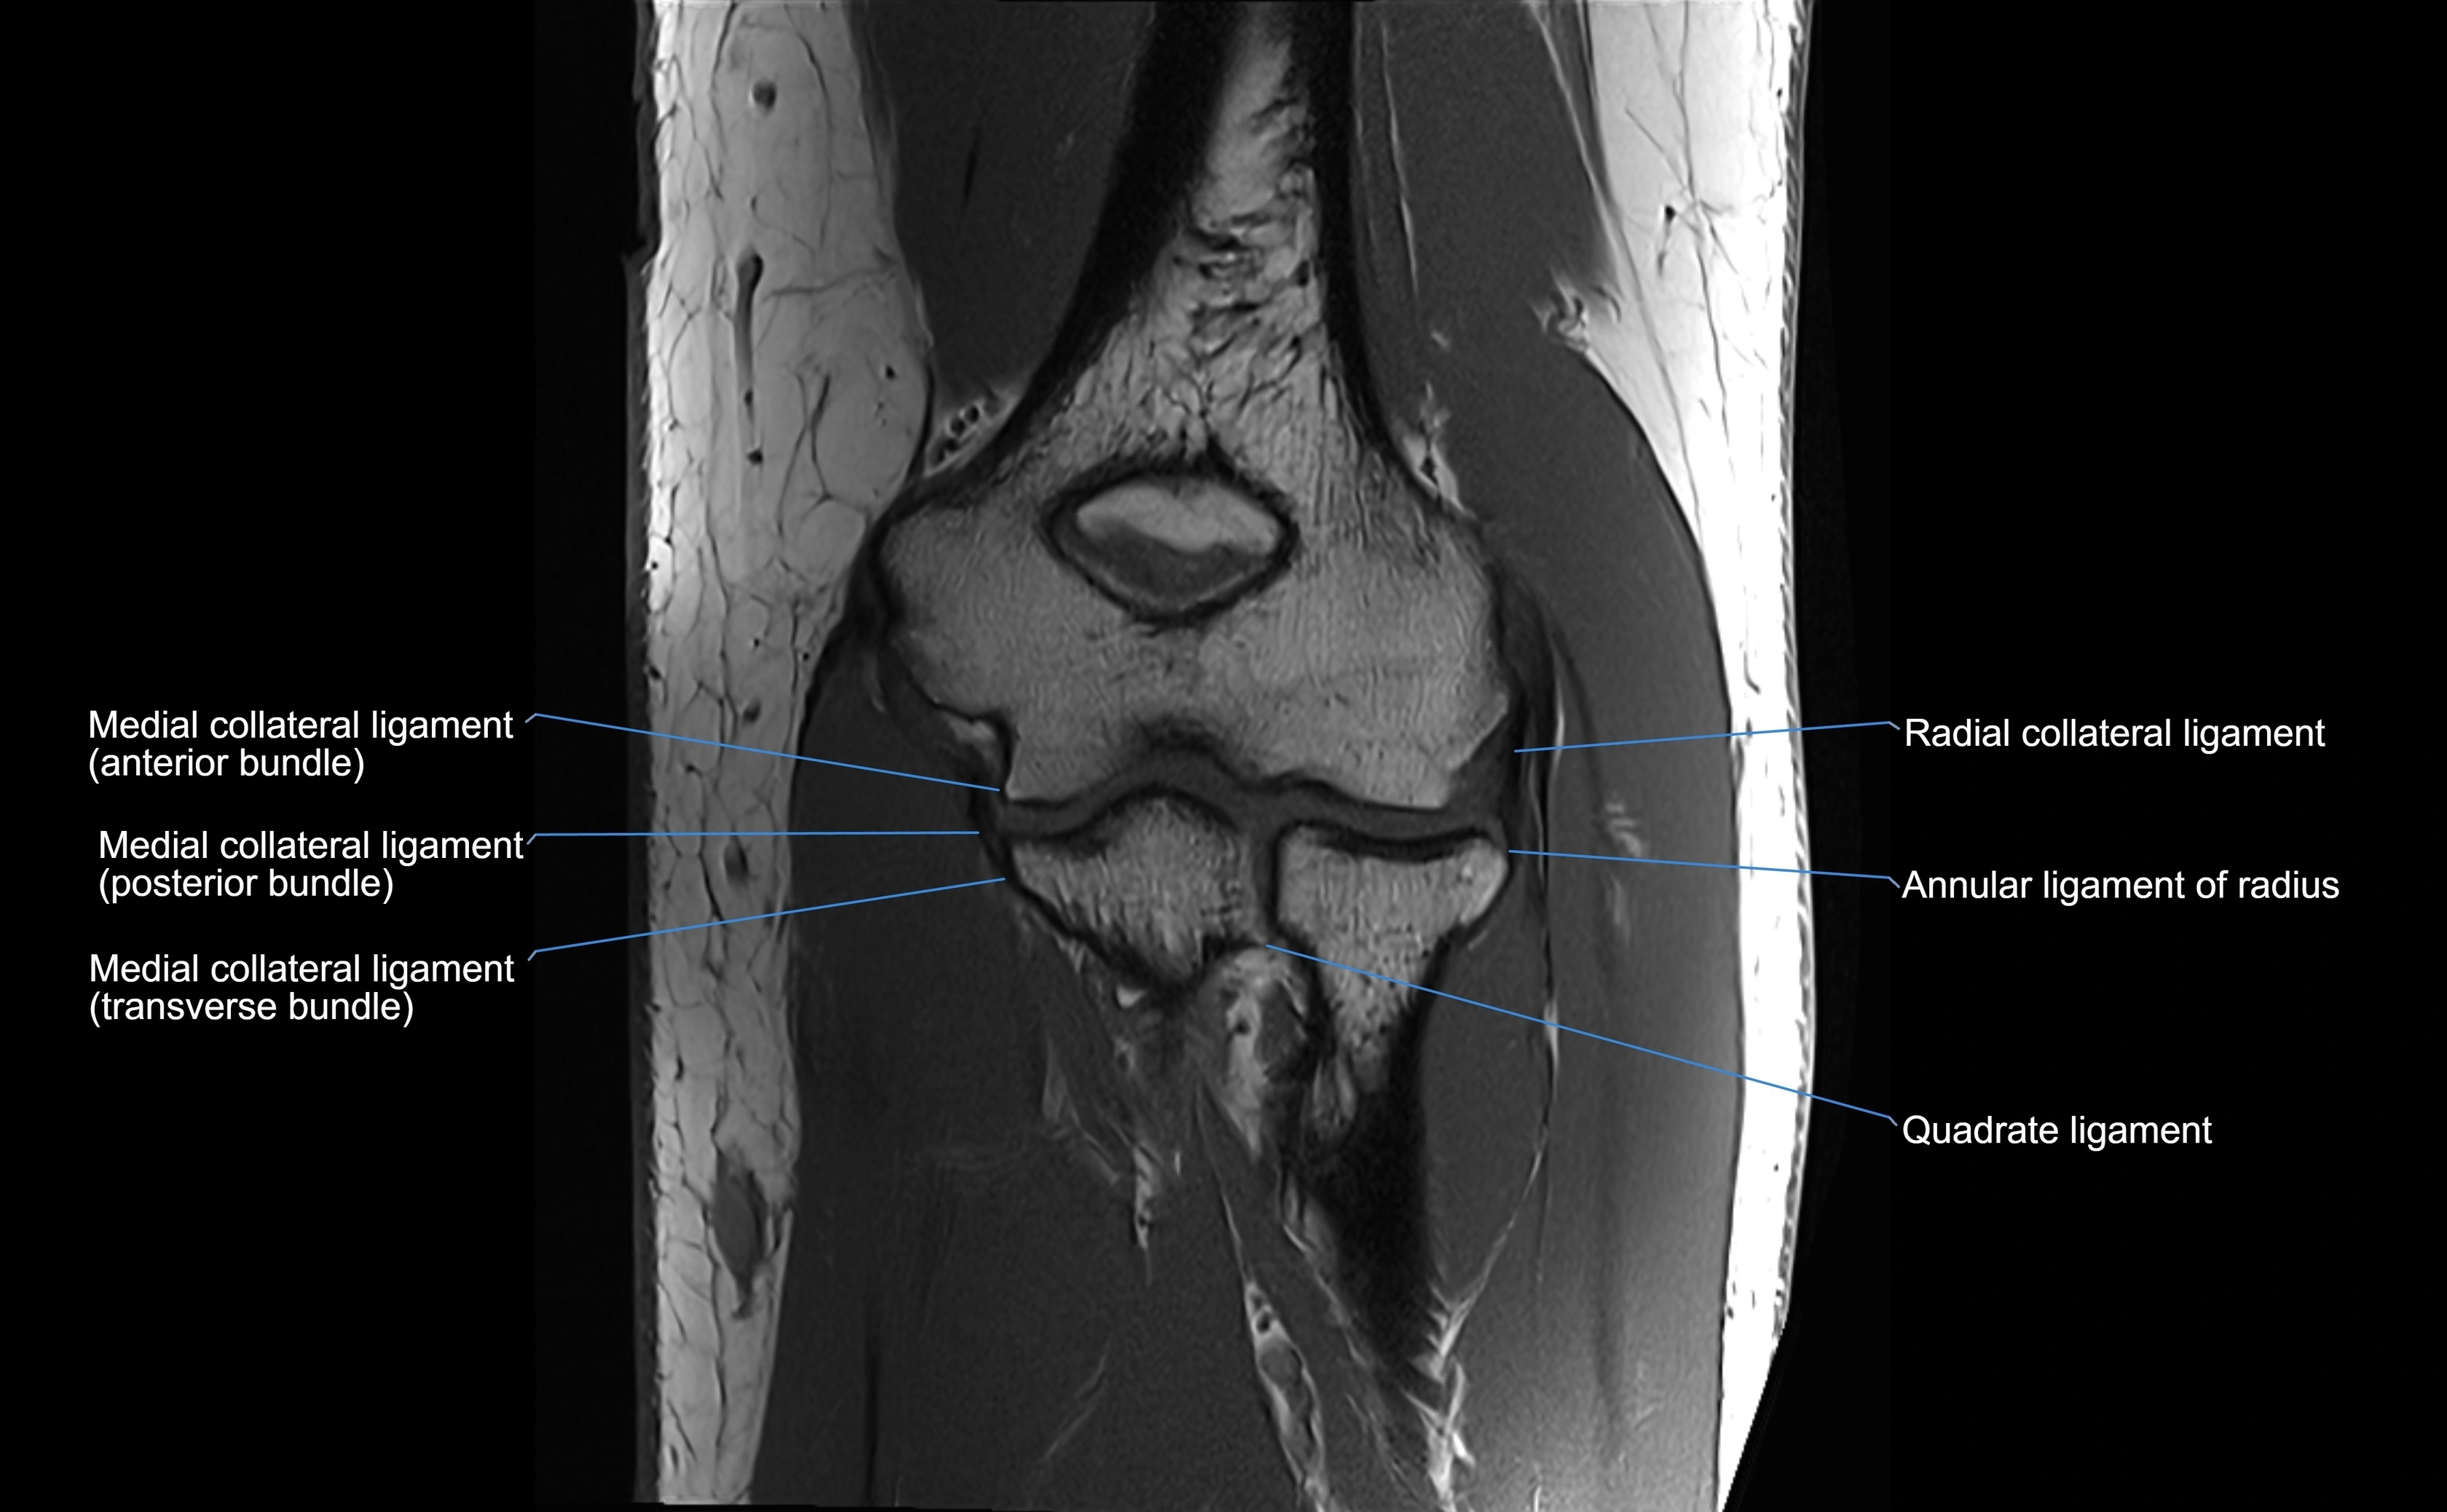

Origin, Course, and Insertion

• Origin: Arises from the anterior margin of the radial notch of the ulna.

• Course: Forms a strong circular band that wraps around the radial head and neck, maintaining them within the radial notch.

• Insertion: Attaches to the posterior margin of the radial notch, completing a fibrous ring around the radial head.

• The inner surface of the ligament is lined with synovial membrane, allowing frictionless rotation.

Relations

• Superiorly: Blends with the capsule of the elbow joint.

• Inferiorly: Supported by the quadrate ligament at the neck of the radius.

• Medially: Attached to the ulnar radial notch.

• Laterally: In contact with the radial head and its articular cartilage.

• Anteriorly: Related to the radial collateral ligament of the elbow.

• Posteriorly: Continuous with the elbow joint capsule.

MRI images

image